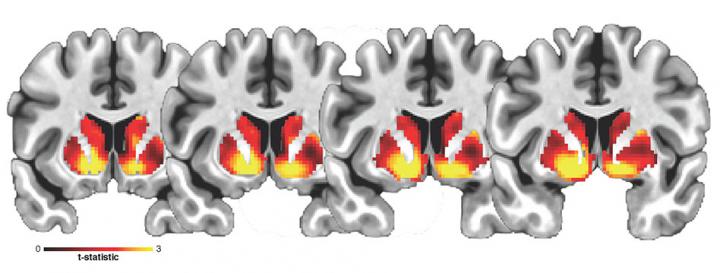

image: Association between cell density at baseline (measured by restriction spectrum imaging) and change in waist circumference one year later. Cellularity in the ventral striatum demonstrates the strongest relationship among all regions in the subcortex.

Image modified from Rapuano, Laurent et al. PNAS 2020

Differences in the microstructure of the nucleus accumbens (NAcc), a region in the brain that plays an important role in processing food and other reward stimuli, predict increases in indicators of obesity in children, according to a study funded by the National Institute on Drug Abuse (NIDA) and nine other institutes, all part of the National Institutes of Health. The paper, published today in the journal Proceedings of the National Academy of Sciences, is based on data from the Adolescent Brain Cognitive Development (ABCD) Study. The ABCD Study will follow nearly 12,000 children through early adulthood to assess factors that influence individual brain development and other health outcomes.

Findings from this study provide the first evidence of microstructural brain differences that are linked to waist circumference and body mass index (BMI) in children. These microstructural differences in cell density could be indicative of inflammatory processes triggered by a diet rich in high fat foods.

Evidence from past human imaging studies has demonstrated the relationship between the NAcc and unhealthy eating behavior in adults. In this study, the researchers leveraged new diffusion MRI imaging techniques to examine the cellular structure of areas that comprise the striatal reward pathway in the brain to investigate disproportionate weight gain in youth.

This study included data from 5,366 ABCD Study participants, ages 9- to 10-years-old at baseline, of whom 2,133 returned for a one-year follow-up visit. The mean waist circumference of the participants, used here as a measure of body fat, increased an average of 2.76 centimeters per participant from the baseline through the one-year follow-up. The researchers used a noninvasive MRI technique to show that an alleged marker of cellular density in the NAcc reflected differences in waist circumference at baseline and predicted increased waist circumference at one-year follow-up.